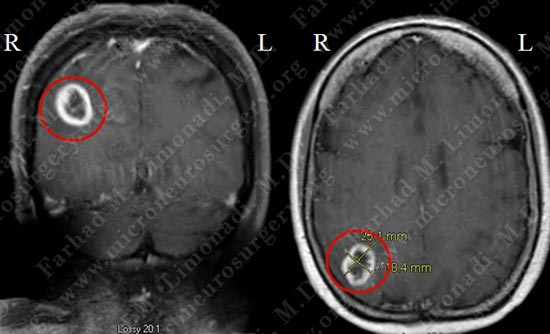

Imaging

MRI scan of patient's brain shows a right parietal ring enhancing tumor (within the red circle) with significant vasogenic edema and local mass effect.